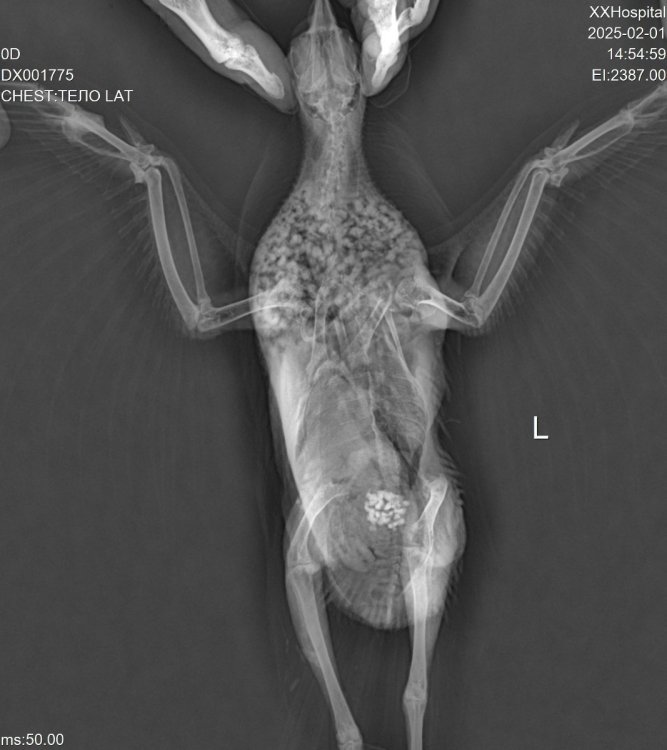

Вечер добрый! Мы наконец повторили рентген. @Zosia не могли бы взглянуть, пожалуйста?

DX001775_1.jpg

DX001775_2.jpg

DX001775_3.jpg

На снимке странно выглядит зона,где должен находиться коракоид. Возможно имеем его перелом. Если это так- то понятно отсутствие возможности летать и общая вялость,т.к. это чрезвычайно болезненный перелом и опасный...

Почему на правом крыле вы видите "шишку"- непонятно. Внешне сустав (локтевой) правого крыла без изменений.

Вообще все положение тела птицы несколько "скособочено" вправо... возможно был плоский удар (машина), и имеются отечные явления

,посттравматические.

Из-за несколько скривленного положения тела на латеральной проекции (праволатеральная) позвононик странно расположен, "фрагментарно", с S-образным изгибом.

Поэтому вопрос- птица какает нормально? Т.е. стандартно порциями, а не постоянным изливом фекалий?

Череп на ВД снимке без патологий.

На лат проекции есть некие объекты, в зоне гонад/яичника, больше похожие на гранулемы яичника .

Пока кроме продолжения терапии НПВС, миорелаксантами, витаминами В6 и В12, источниками кальция- нечего добавить (по части преджполагаемой травмы).

Из общей терапии (противомикробной)- вы курс метронидазола наверное уже пропили, не помню- пили ли энтерофурил (если не пили- пропить).